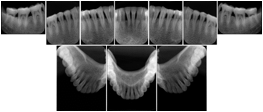

Intra-oral radiography typically involves acquisition of multiple images of various parts of the dentition. Many digital radiographic systems offer customized templates that are used for displaying the images in a study on the screen. These templates may also be referred to as mounts or view sets. The Structured Display Object represents a standard method of encoding and exchanging the layout and intended display of Structured Displays. A structured display object created in this manner could be stored with a study and exchanged with images to allow for complete reproduction of the original exam.

In most standard cases, images are oriented in structured layouts. These structured displays are useful to be shared between providers for reference purposes.

Table OO.1.1-1 shows structured display standard templates, where Viewset ID is based on the Japanese Society for Oral and Maxillofacial Radiology (JSOMR) classification provided by JIRA (Japan Medical Imaging and Radiological Systems Industries Association, www.jira-net.or.jp). Expected or typical teeth to be imaged location, region and designation codes are based on ISO 3950-2010, Dentistry - Designation system for teeth and areas of the oral cavity. For all the hanging protocols listed in OO.1.1-1, the value to use for Hanging Protocol Creator (0072,0008) is "JSOMR" and the value to use for Hanging Protocol Name (0072,0002) does not include "JSOMR" (e.g., "DL-S001A", not "JSOMR DL-S001A").